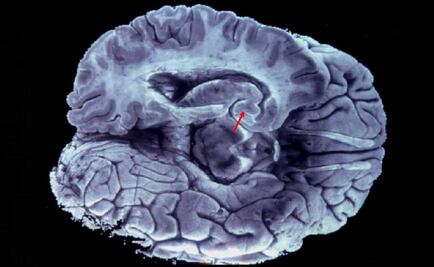

En el Centro Médico La Raza se detectan en promedio cuatro o cinco casos de tumores malignos de mama al año; de cada mil diagnosticadas, una está en periodo de gestación